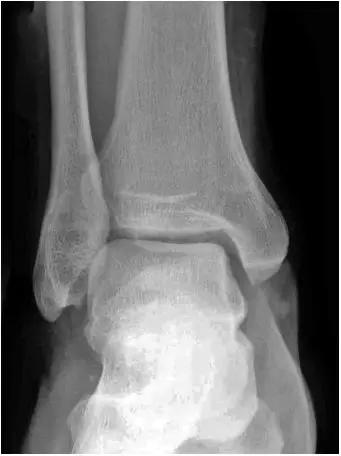

- 放射学表现主要为胫骨前下缘与距骨颈部前上缘鸟嘴样骨刺形成。

放射学表现主要为胫骨前下缘与距骨颈部前上缘鸟嘴样骨刺形成

- Ⅰ度:滑膜撞击,X线片显示有炎性反应,骨刺大小为3mm;

- Ⅱ度:骨软骨反应性骨赘>3mm;

- Ⅲ度:严重的外生骨赘,可伴有或不伴有碎裂, 在距骨背侧可见继发性骨赘,常伴有骨赘的碎裂;

- Ⅳ度:距骨和胫骨关节骨性关节炎改变。